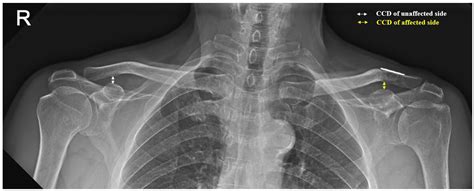

Interpreting the results of an Ac Joint X Ray requires a trained eye. Radiologists look for specific signs and abnormalities that indicate various conditions. Here are some key points they consider:

• Joint Space: The space between the clavicle and scapula should be uniform. Any narrowing or widening can indicate injury or degeneration.

• Bone Alignment: The bones should be properly aligned. Any displacement or misalignment can suggest a fracture or dislocation.